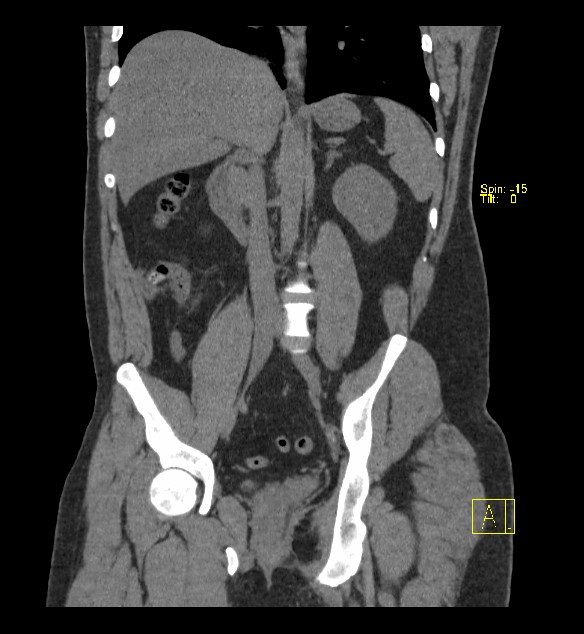

La TAC presenta mayor sensibilidad y especificidad (94 y 95% respectivamente) que la ecografía (86 y 81% en cada caso). Además se considera la prueba de elección en pacientes con obesidad importante.